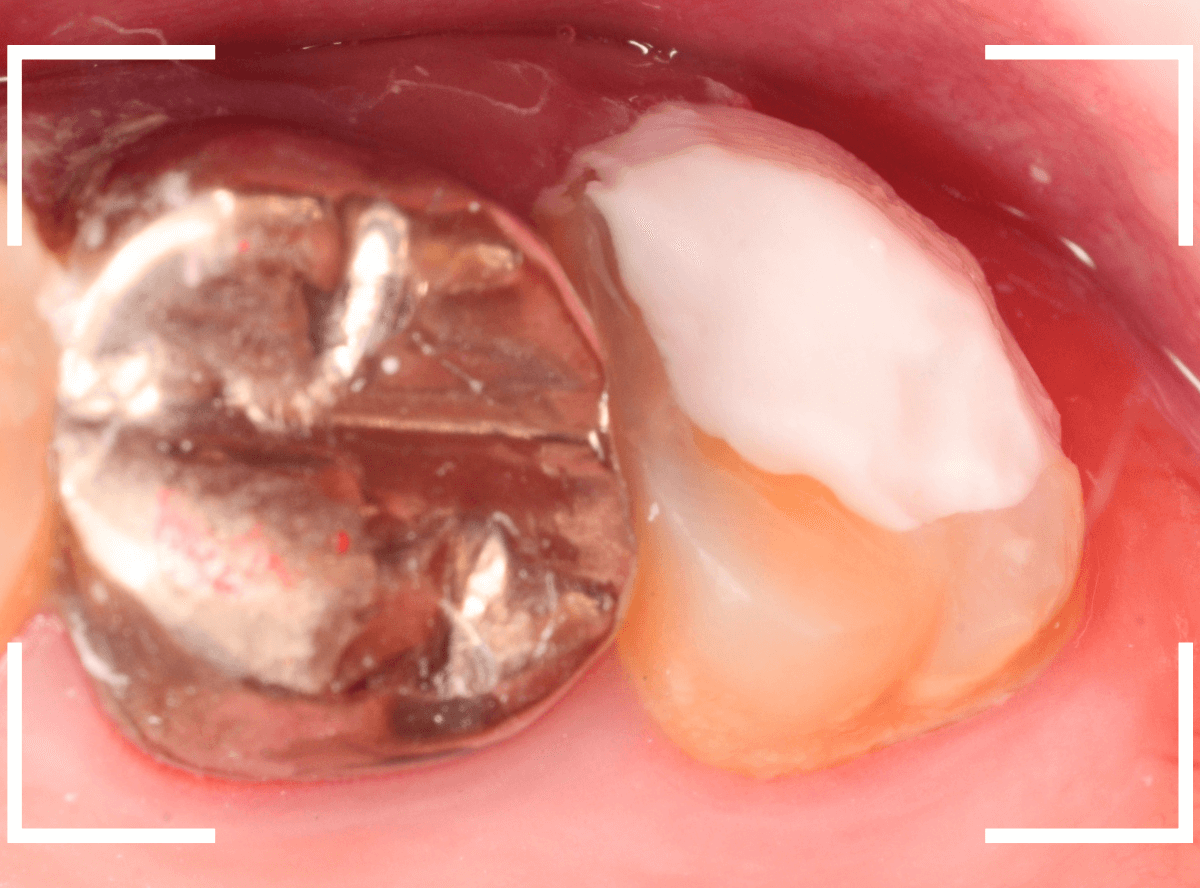

Case.12 下の一番奥の歯が、奥からひどい虫歯

「下の一番奥の歯が痛い」という訴えで来院された患者さんの例です。

一見では、特に問題ないように見えます。

電気メスで、虫歯周囲の歯肉を除去後、全ての虫歯を除去しました。

虫歯は深かったですが、なんとか神経寸前のところで食い止められました。

神経を保護するお薬をつめて、セメントで蓋をしてしばらく経過観察します。

経過観察後、痛みがない事が確認できれば、つめものを作製します。